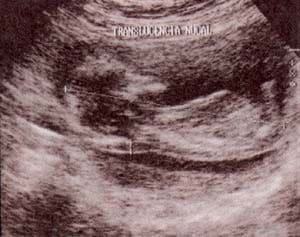

fig 10. – (a). determinación de la translucencia nucal. corte sagital. la medida se realiza entre la parte externa del tejido que recubre la columna a nivel cervical y la parte interna de la piel (flecha superior).

es fundamental obtener una clara identificación del amnios el cual flota libremente (flecha inferior). en la cavidad amniótica hasta la semana 16 cuando se fusiona completamente con el corion.

| fig. 10. – (b) traslucencia nucal normal y patológica. 11. semanas: traslucencia nucal en feto cromosónicamente normal. | fig. 10. – (c). 12. semanas: traslucencia nucal patológica en feto afecto de trisomía 21. |